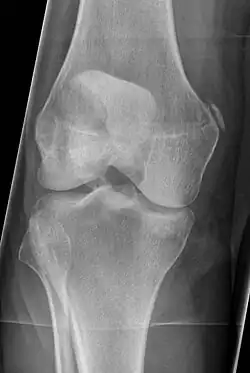

Pellegrini–Stieda syndrome (also called Stieda disease and Köhler–Pellegrini–Stieda disease) is the ossification of the superior part of the medial collateral ligament of the knee. It is a common incidental finding on knee radiographs. It is named for the Italian surgeon A. Pellegrini (b. 1877) and the German surgeon A. Stieda (1869–1945).[1] While the eponym refers to Pellegrini and Stieda, the condition was first discovered by Köhler in 1903, before any namesakes. Pellegrini-Stieda combines the aforementioned radiographic findings and concomitant medial knee joint pain or restricted range of motion.[2]

Diagnosis is typically made on radiographs demonstrating the Pellegrini-Stieda syndrome sign accompanied by pain or restriction of range-of-motion of the knee joint.[2] Pellegrini-Stieda syndrome sign is typically described by a longitudinally linear opacity, which is a process that is describes characteristic of calcification in the soft tissue located medial to the medial femoral condyle.[2] This calcification seen on imaging represents the ossification of the medial collateral ligament, which typically does not develop until approximately three weeks after the initial injury.[2]It is important to note to distinguish this radiographic finding from that of a medial femoral condyle avulsion fracture, which is an injury in which a pulling force of a tendon or ligament fractures away a piece of the bone from its attachment site.[2]

Alternative classification syndrome for Pellegrini-Stieda lesions of Type 1 through Type 4 based on their location:[2]

- Type 1- is referred to as a beak-like appearance and describes the ossification arising from the femur and extending inferiorly in the medial collateral ligament.

- Type 2-is defines a tear-drop pattern, localized within the medial collateral ligament without any attachment to the femur.

- Type 3-presents as an elongated ossification superior to the femur lying in the distal adductor magnus tendon.

- Type 4-is also characterized as a beak-like appearance arising from the femur. However, there are some cases where this ossification extends into both the medial collateral ligament and adductor magnus tendon. In then, the original attribution of the syndrome to the medial collateral ligament may now be outdated as many publications have suggested concomitant and even sometimes preferential involvement of the adductor magnus tendon, medial head of the gastrocnemius, or medial patellofemoral ligament.[2]